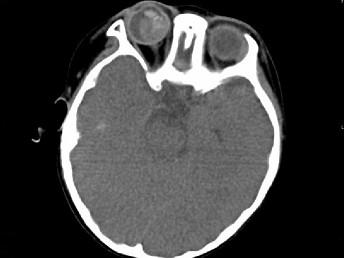

问题 男,2岁、右眼白瞳症一个月,CT影像如图,最可能的诊断为 ( )

选项 A、Coats病 B、视网膜母细胞瘤 C、永存原始玻璃体增生症 D、脉络膜骨病 E、眼球内寄生虫病

答案 B